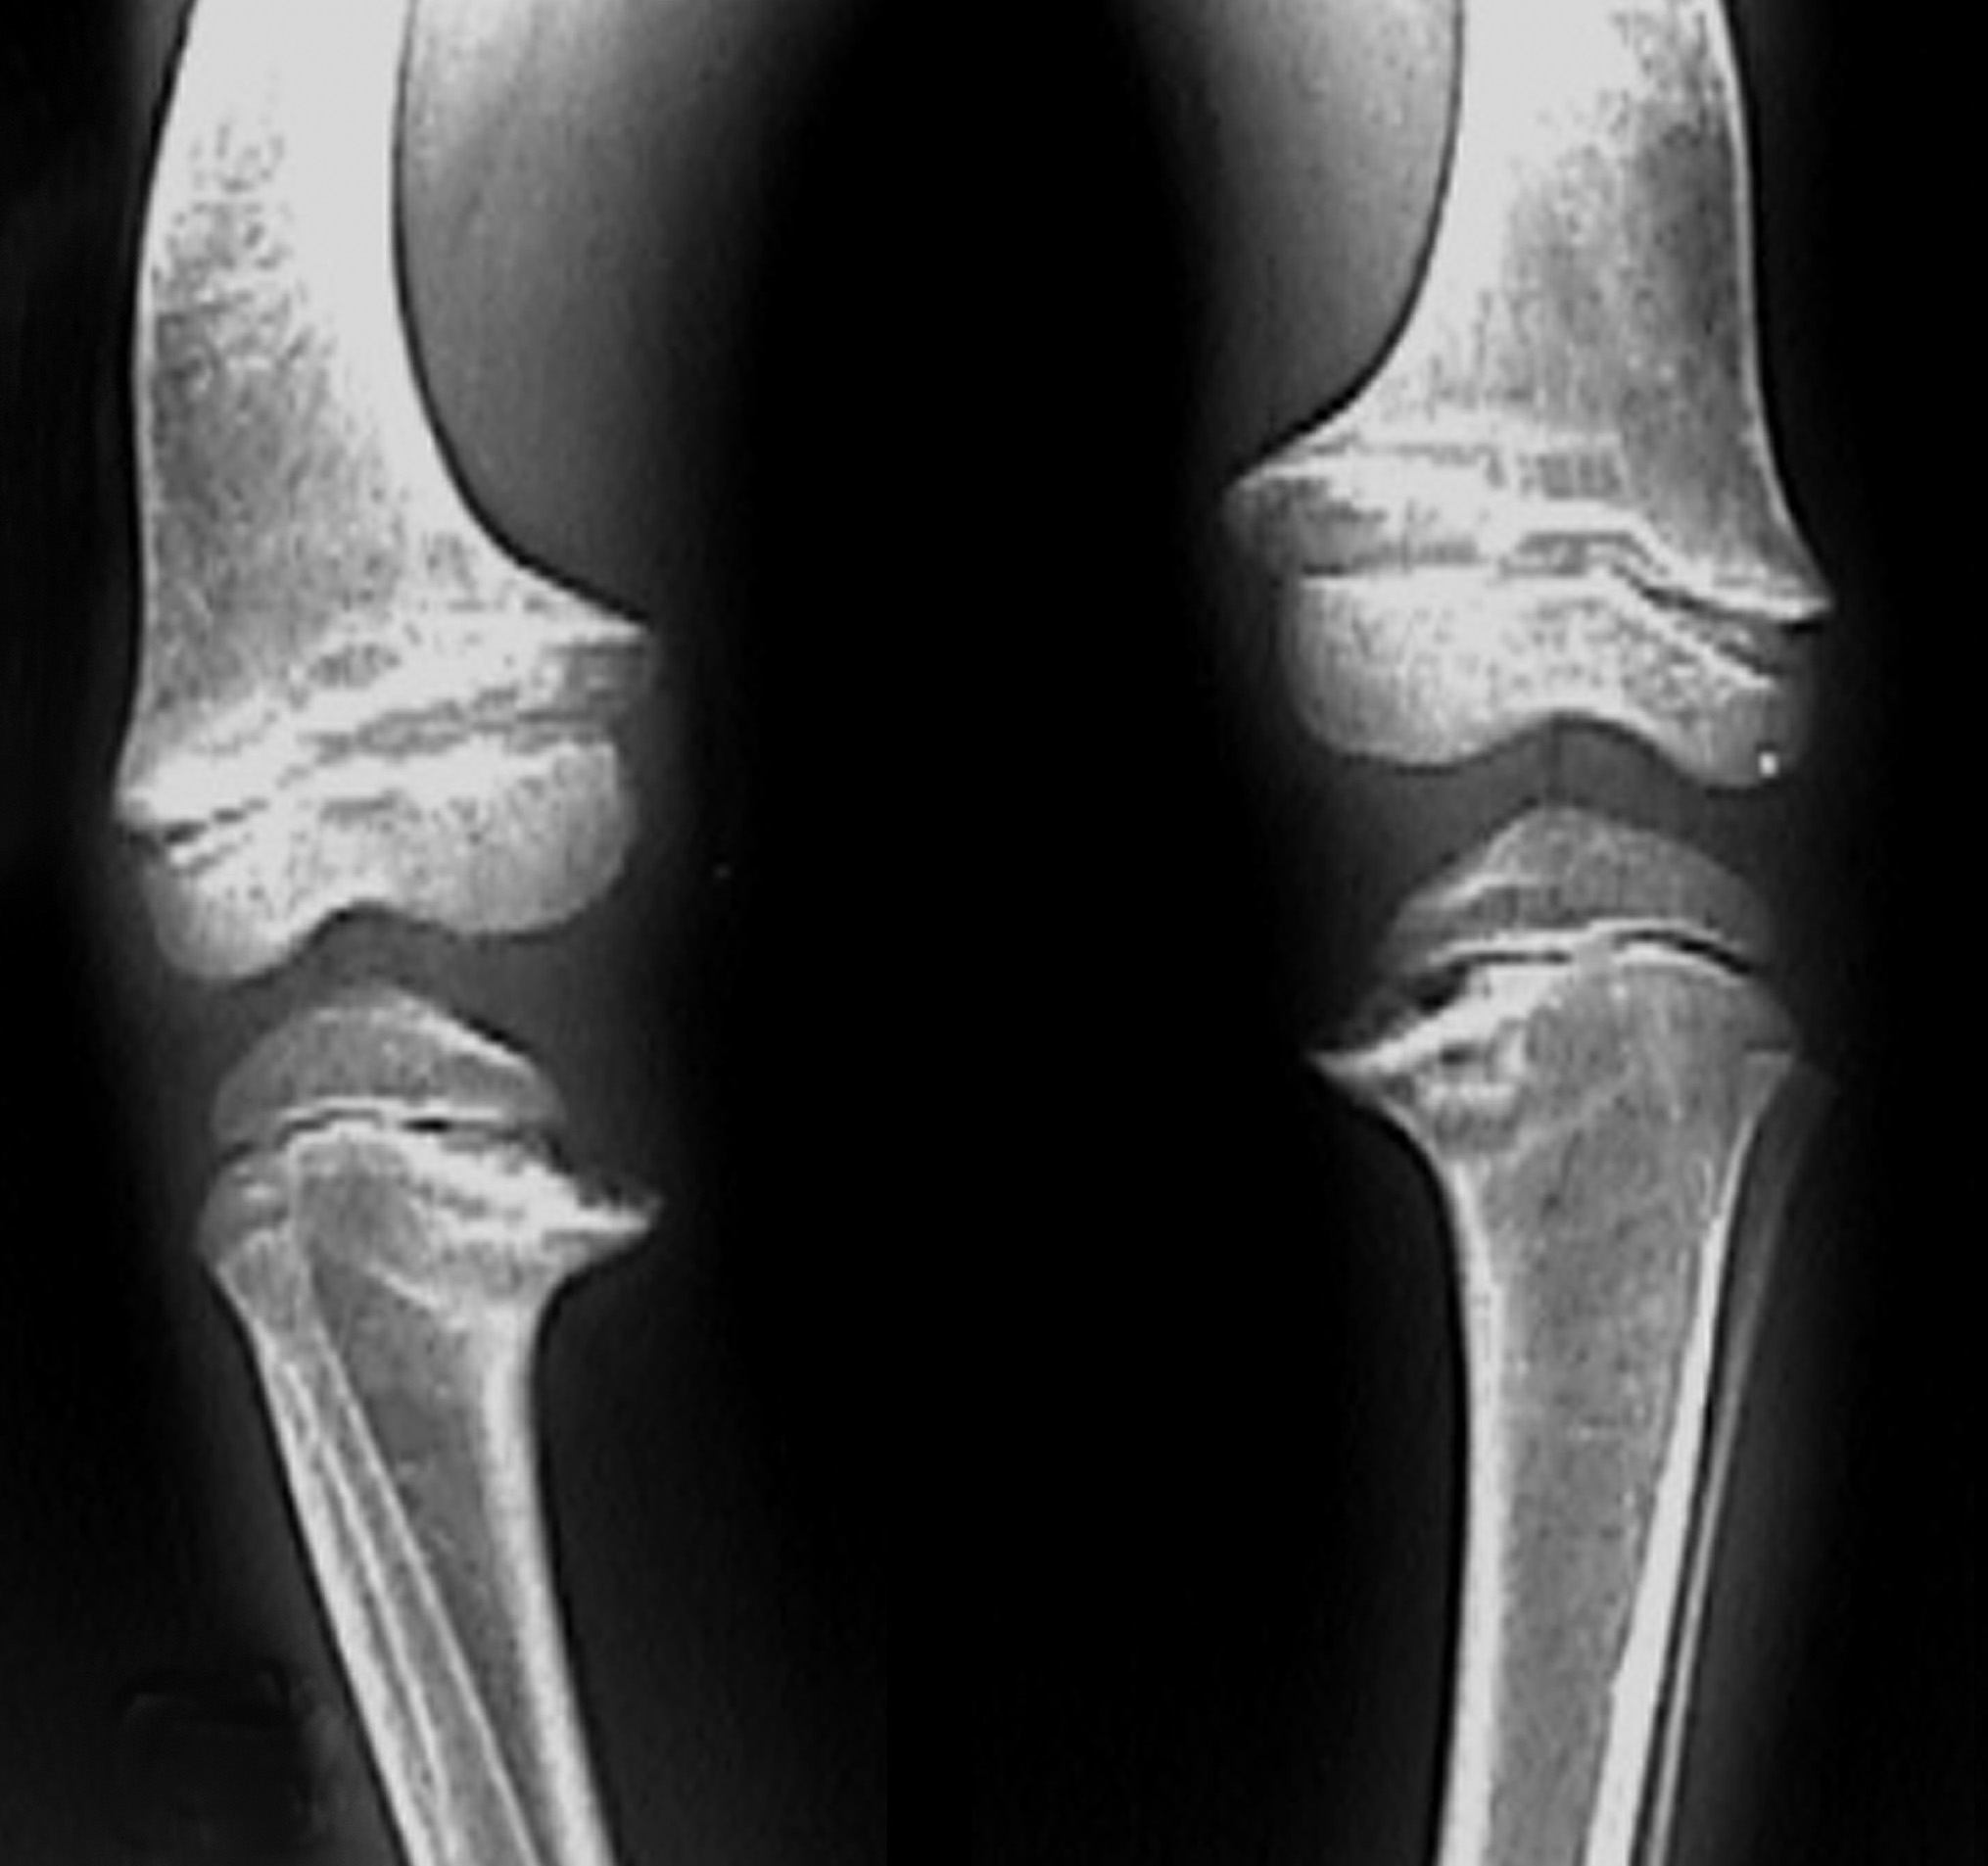

Radiographs of the patient's knees, the left knee alone, and the left wrist are obtained.

The radiograph of the knees shows bilateral genu varum and widening of all the tibial and femoral physes (A, orange arrows); there is also prominent sclerosis adjacent to the physes, primarily located in the medial portions of the metaphyseal tibiae and femora (A, black arrows). The radiograph of the left knee better demonstrates the physeal widening (B,orange arrows) and the juxtaphyseal sclerosis (B, black arrows). The radiograph of the left wrist shows widening of the distal radial physis with flaring of the distal radial and ulnar metaphyses (C,orange arrowheads); sclerosis adjacent to the radial and ulnar physes is most prominent in the distal radial metaphysis (C, black arrows). A prominent anterior costochondral junction caused by the preponderance of the maturing cartilage can also occur in persons with rickets.